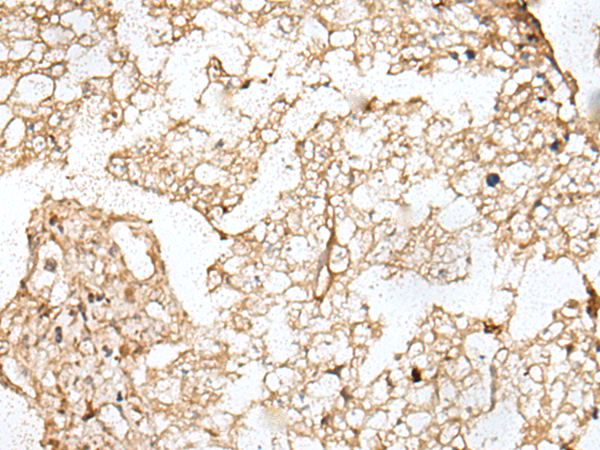

- The image is immunohistochemistry of paraffin-embedded Human lung cancer tissue using P12702(KNL1 Antibody) at dilution 1/20. (Original magnification: ×200)